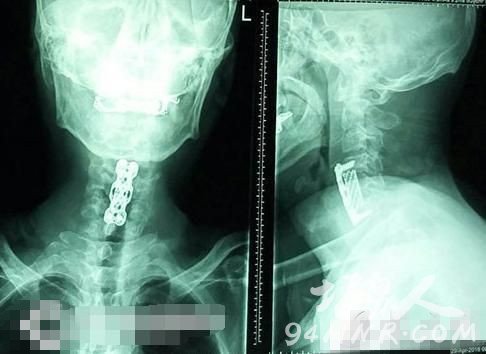

瞿杭波医生说,颈椎病分四大类:颈型,症状(脖子痛)、神经根型(手痛手麻)、脊髓型颈椎病(肌肉反射亢进、手抖、走路不稳)、血管性颈椎病(头晕、恶心)。低头族大部分是颈型颈椎病,后面三类都是这类颈椎病的加重型。

“如已确诊为脊髓型颈椎病的患者,要少低头及过度仰头,及早到医院让医生评估是否有手术指征,如果可能的话及早手术,防止意外事件的发生。平时也要加强颈椎肌肉力量的锻炼。”瞿杭波医生说,总是感觉脖子痛、手麻手痛的人,一定要马上去医院,等到走路不稳时,颈椎病往往已到了晚期。